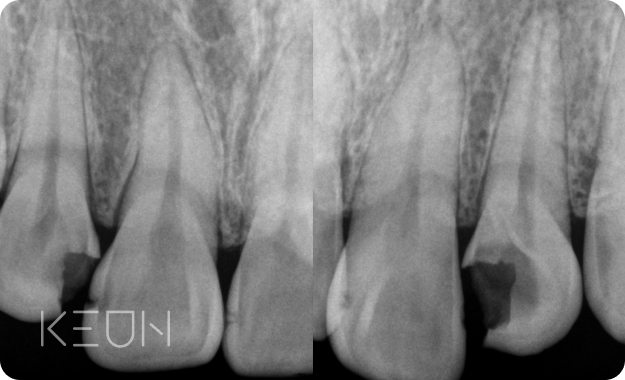

눈에 잘 보이는 충치는 육안과 파노라마로도 충분히 진단이

가능하지만 치아 사이에 발생한 충치는 발견하기 어렵습니다.

3차원 CT를 통해 치아의 뿌리와 신경의 위치, 충치의 위치 등을

정확히 파악 후 치료할 수 있습니다.